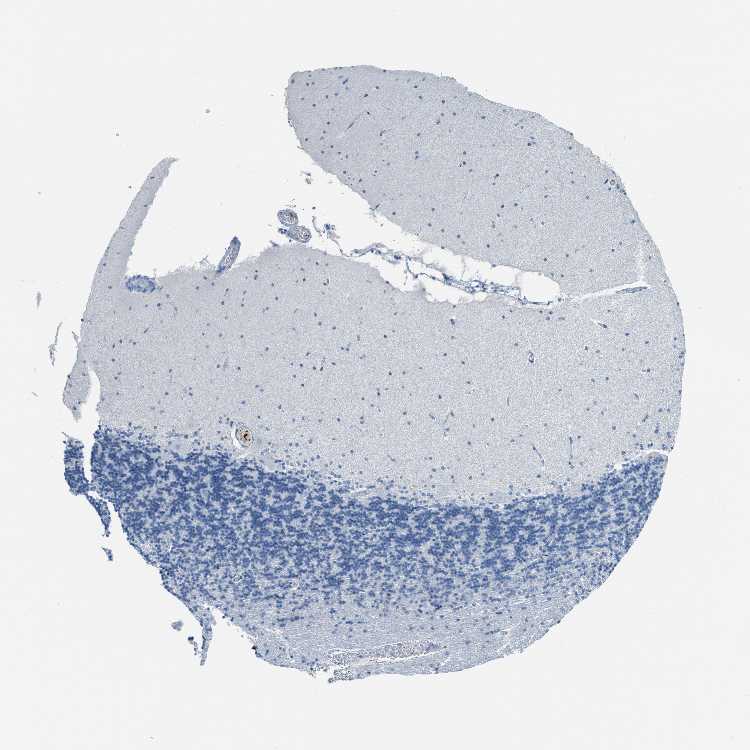

CEREBELLUM - Antibody stainingi

Antibody staining in the annotated cell types in the current human tissue is reported as not detected, low, medium, or high, based on conventional immunohistochemistry profiling in selected tissues. This score is based on the combination of the staining intensity and fraction of stained cells.

Each image is clickable and will lead to virtual microscopy that enables deeper exploration of all samples and also displays staining intensity scores, fraction scores and subcellular localization as well as patient and tissue information for each sample.

Antibody HPA008354Antibody CAB017624

Purkinje cells Not detectedNot detected

Cells in granular layer Not detectedNot detected

Cells in molecular layer Not detectedNot detected